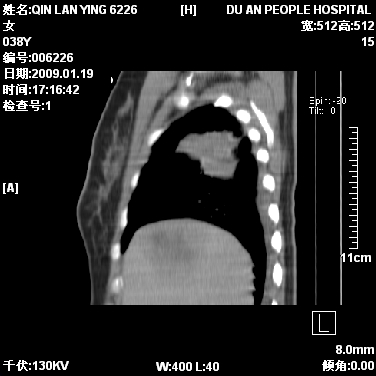

女,38岁,胸疼1个月。wbc:1万4

1)右肺中央型肺癌并右肺上叶阻塞性肺炎、节段性肺不张,纵隔淋巴结转移、右侧胸膜转移、肝脏转移。2)右侧胸腔少量积液。

1、右侧中央型肺癌并阻塞性肺不张,纵隔内、主动脉弓旁、右肺门淋巴结及肝脏转移可能性大,建议纤支镜进一步检查。

2、右侧胸腔积液。

本病例有几个容易诊断的地方:1、右肺上叶前段支气管闭塞,肺不张。2、淋巴结明显肿大。3、肝脏多个类圆形低密度影呈“牛眼征”改变,高度提示转移。

从影像学角度分析      右肺上叶中央型肺癌,并阻塞性不张、肺炎,纵隔淋巴结、膈顶淋巴结转移。

肝内两个大小不等低密度结节,内可见更低密度影,首先考虑肝内转移瘤,但联想到患者wbc1万4,建议楼主还是做个增强比较明确,除外肝脓肿的可能。